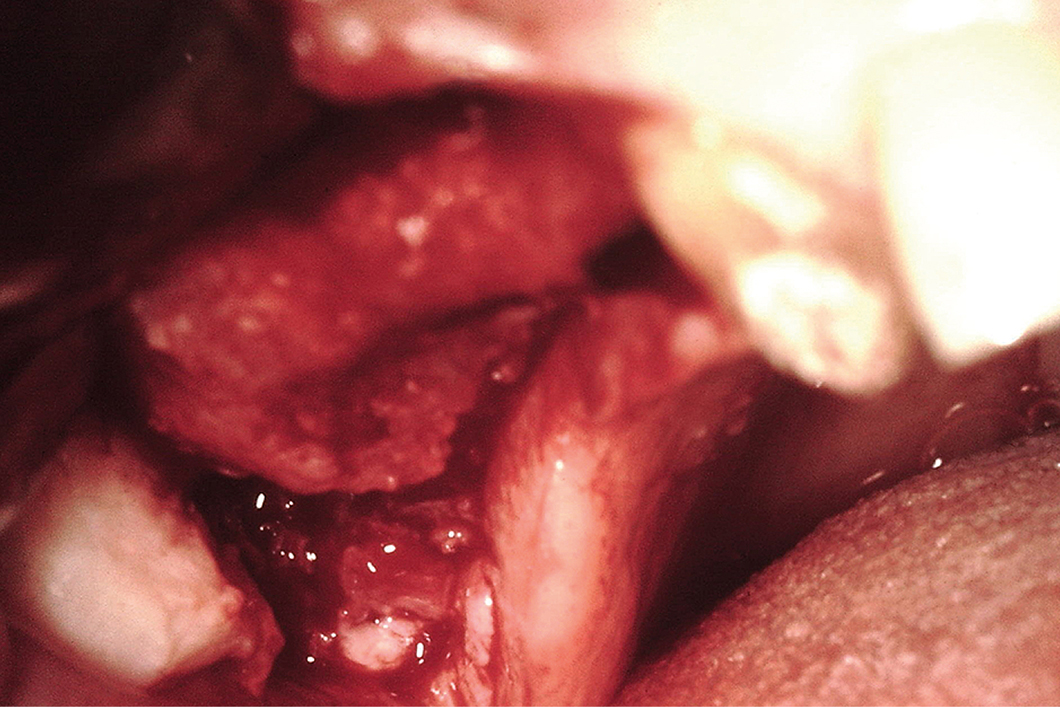

Ein schwieriger Fall einer oralen Rehabilitation mit einer besonderen Herausforderung in den Regionen 15 und 16. Der Patient hatte einige Jahre zuvor einen Autounfall gehabt und war in diesem Bereich verletzt worden. Dies führte zu einer anatomischen Veränderung des Sinus mit teilweisem Verlust der bukkalen Sinuswand und Narbengewebe in einem Teil des Sinus.

Während der Aufklappung wurde das Narbengewebe freigelegt und zum Teil entfernt. Nach diesem Schritt wurde eine Geistlich Bio‑Gide® Membran eingebracht, um das im oberen Teil der Sinushöhle vorhandene fibrotische Gewebe zu isolieren. Dann wurde die Schneidersche Membran in der mittleren Region des Sinus angehoben. Die Sinushöhle wurde mit Geistlich Bio‑Oss® gefüllt, das auch zur Regeneration des Kieferkammdefekts verwendet wurde. Geistlich Bio‑Gide® wurde bukkal mit Knochennägeln stabilisiert und unter den palatinalen Lappen gestopft.